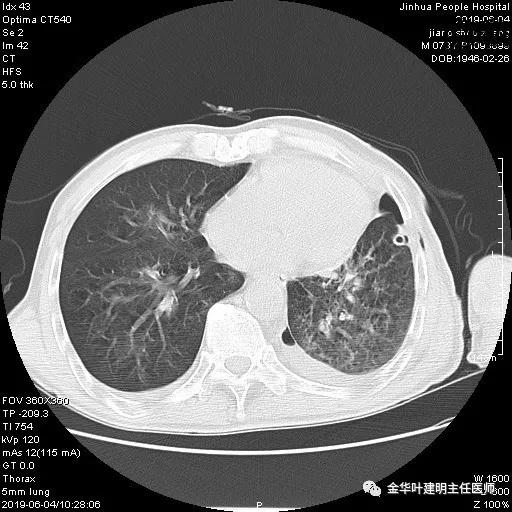

6.1上午:24小时胸液量约1700毫升,但血压一直较平稳,心率不快。发现胸液中有乳白色液体,静置下处于上层,斟酌乳磨性胸液,故拟予以禁食,并使用生长抑素抑制消化液分泌,予以静脉高营养支持治疗;

6.2上午:血色素8.7 g/L,禁食下24小时胸引量仍达950毫升;此时知道不是胸内活动性出血,而是乳糜胸,相对来说,情况就没有大出血那么紧急。注意力转移到乳糜胸的处理上来;

6.4上午:24小时引流出血性乳糜液1800毫升。是否再次手术进行右进胸胸导管结扎,抑或继续保守治疗非常纠结!压力非常大!!多方讨论会诊无法取得一致意见,但一般认为,引流量在1000毫升以上宜积极手术。情况与浙二医院范军强教授联系,请求指导,范教授认为左侧肺手术,损伤胸导管主干的机会较小,多数可保守治疗而愈。在他们的病例中,也有结扎胸导管后引流量仍无减少,效果并不能完全保证。建议能够斟酌胸管夹管观察(因为淋巴管压力低,予以适当的压力,漏出量可能会明显减少),同时继续禁食,并静脉营养支持,引流管口可能会有渗液,注意更换敷料。与家属充分沟通后决定试夹管;这天血色素9.0 g/L;胸部CT复查示: